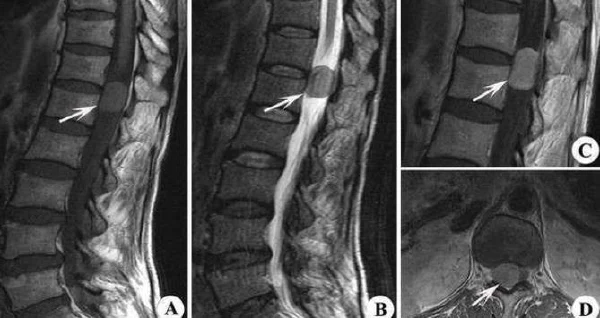

脊髓肿瘤,是生长在脊髓或其周围的中枢神经系统肿瘤。根据位置,脊髓肿瘤主要分为髓内肿瘤、髓外硬膜下肿瘤和硬膜外肿瘤。不同类型的脊髓肿瘤会对患者产生不同程度的神经功能损伤,甚至影响生命。

根据该患者的症状—右上肢麻木、走路不稳、下肢无力,可以推测,她可能具体患有的是脊髓内肿瘤。这种肿瘤的位置在脊髓的实质内,最常见的是星形细胞瘤和室管膜瘤。

脊髓肿瘤的治疗方法主要包括手术、放疗和化疗等。手术是首选治疗方法,通过手术切除肿瘤,减轻神经压迫,缓解症状。对于位于脊髓内的肿瘤,可以通过显微手术技术进行精细操作。